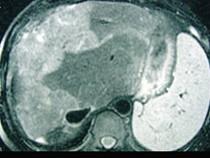

问题 女性,72岁,腹胀不适1年,加重伴恶心、呕吐、乏力1个月,影像检查如图,最可能的诊断为 ( )

选项 A.肝硬化腹水 B.原发性肝癌 C.肝血管瘤 D.巴-希综合征 E.局灶脂肪肝

答案 D